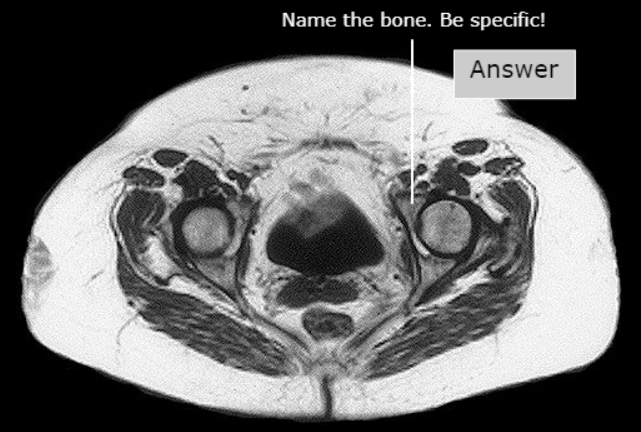

Pubis